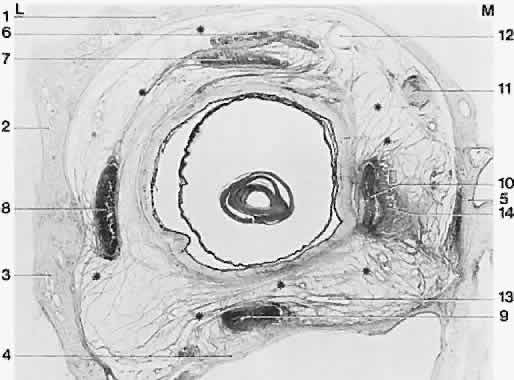

The trochlea (pulley) of the superior oblique constrains the tendon and changes its direction of pull so that a new origin is created. Less dramatic accumulations of fibrous orbital tissue surround the rectus muscles just behind the equator and extend to the orbit holding it to some degree to the orbit wall (Fig. 12). These tissues also act to limit sideslip in the rectus muscle and to limit the surgical effect of rectus muscle transposition operations in which the insertion is moved laterally. They bias the origin as the trochlea does, but to a much lesser degree, thus acting as “soft pulley” (Fig. 13). such displacement occurs in strabismus disorders, but it is not always clear whether the displaced muscle is taking the pulley with it or vice versa. These tissues have long been known to contain smooth muscle fibers.17 Innervation to these structures and their functional significance is a current topic of investigation.

Fig. 12. Frontally sectioned histologic section (60 degree) of an adult right orbit, at a level in the orbit 3.2 mm anteriorly from the posterior pole of the eye. Asterisk, connective tissue septa; 1, frontal bone; 2, greater wing of sphenoid; 3, zygomatic bone; 4, maxilla; 5, ethmoid; 6, superior levator palpebrae muscle; 7, superior rectus muscle; 8, lateral rectus muscle; 9, inferior rectus muscle; 10, medial rectus muscle; 11, superior oblique muscle; 12, superior ophthalmic vein; 13, branches of inferior ophthalmic vein; 14, medial check ligament. Notice size difference of muscles; intermuscular membrane is well developed here. M, medial; L, lateral. Acidic fuchsin-picrin acid/van Gieson stain, original magnification × 2.5. (Koornef L: Arch Ophthalmol 95:1271, 1977.)